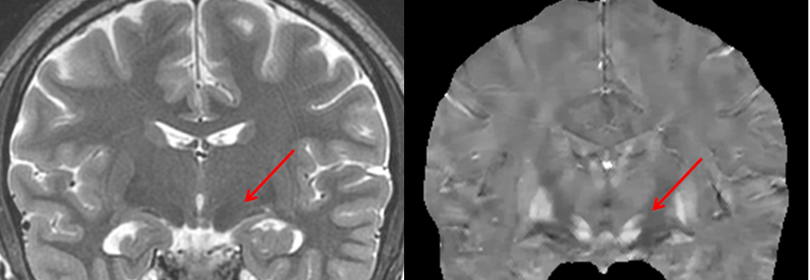

Photo caption: QSMetric can map iron involved in neuron function, including neurotransmitter generation. Deep gray nuclei are highly active in neurotransmitter generation with iron as a cofactor. Traditional T2 weighted imaging (left) depicts iron-rich deep gray nuclei such as subthalamic nucleus (arrow) with blurred hypointensity. QSM (right) depicts subthalamic nucleus with sharp positive contrast. QSM is the method of choice for mapping DBS targets.

Photo credit: Imaging Biometrics